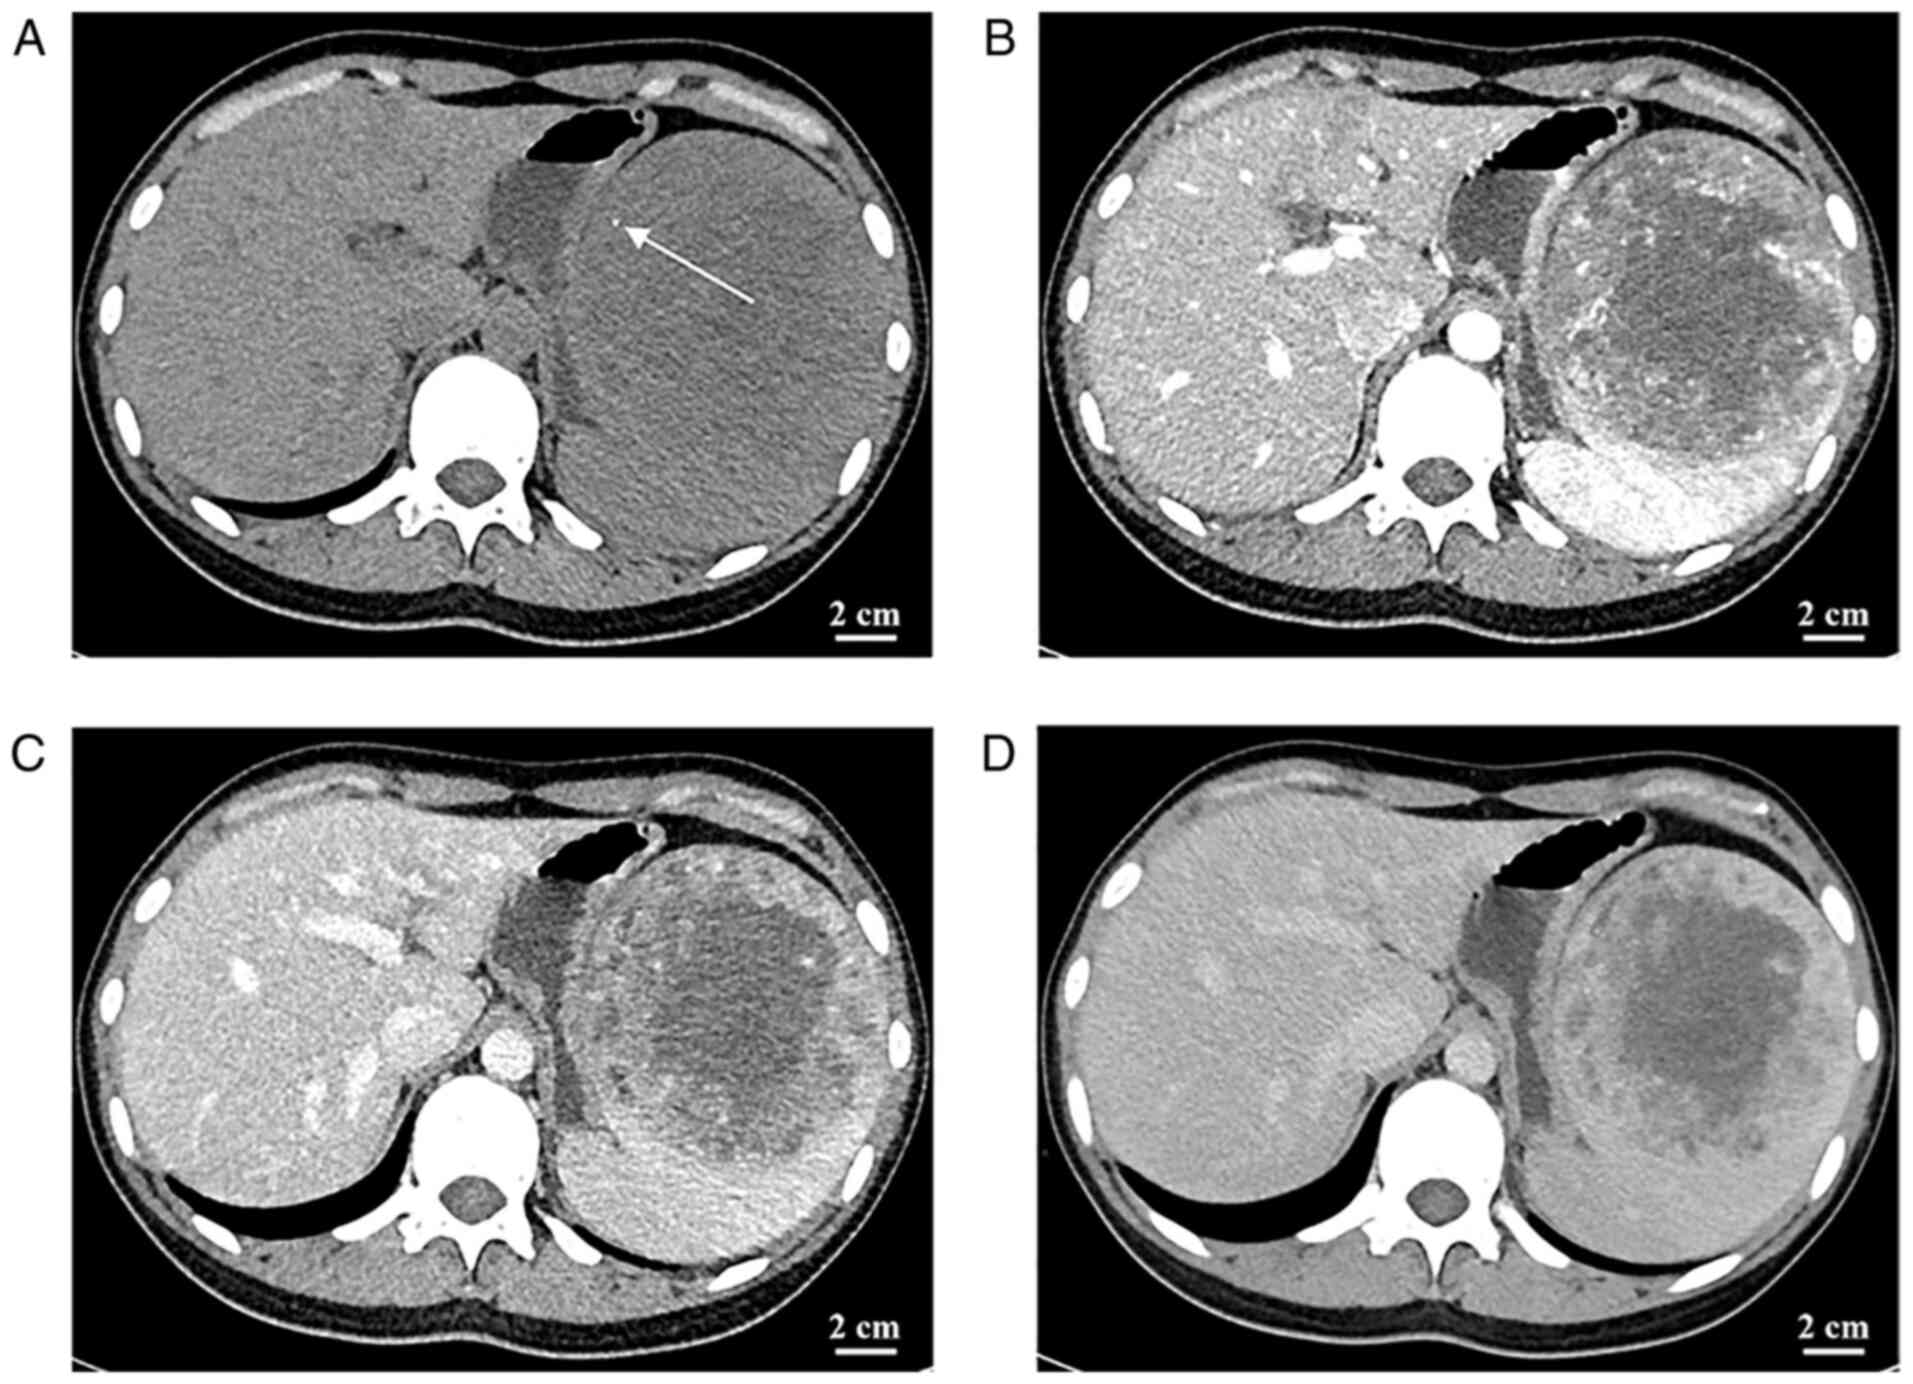

The CT of the abdomen revealed a mass of heterogeneous density with patchy, slightly hyperdense and poorly defined borders. In addition, punctate calcification was observed in the tumor. The parenchymal portion of the tumor had progressive enhancement, whereas the central liquefied necrotic region exhibited no discernible enhancement. The boundary between the tumor and the surrounding tissue was visible following enhancement (Fig. 2). Abdominal CT displayed a slightly hypodense, ill-defined mass. In addition, small patchy hemorrhage as well as calcification were seen within the mass (Fig. 2). Abdominal magnetic resonance imaging (MRI), including conventional MRI and enhanced abdominal MRI, indicated a mixed-signal mass in the spleen, measuring ~10.6×10.6×10.1 cm, with well-defined borders. The tumor margin had an envelope-like structure and the parenchyma exhibited progressive enhancement with no enhancement in the central necrotic area. The parenchymal part of the neoplasm had a high signal (b=1,000 sec/mm2) on diffusion-weighted imaging (DWI) and a low signal on the apparent diffusion coefficient map, suggesting that the spread of the parenchymal part of the neoplasm was restricted; by contrast, the central necrotic area was not restricted (Fig. 3). The radiologist initially diagnosed a vascular tumor originating from the spleen, such as hemangioma, based on this patient's clinical presentation and the imaging features. However, it was not possible to exclude other benign or malignant neoplastic lesions.

Figure 3.

(A) MRI scan revealing a round mass-like mixed signal in the spleen, with mixed iso-signal and hypo-signal on T1WI. (B) T2WI indicates a predominantly iso-signal mixed signal in the parenchymal part and a predominantly hyper-signal in the internal necrotic and liquefied area. (C) The parenchymal portion of the tumor displays with a heterogeneous hyper-signal on diffusion-weighted imaging (b=1,000 sec/mm2), while the central area of liquefied necrosis displays as a hypo-signal. (D) The central liquefied necrotic area displayed as a hyper-signal on the apparent diffusion coefficient map. (E) Progressive enhancement in the parenchymal part and (F) no significant enhancement in the central liquefied and necrotic area (scale bar, 2 cm). T2WI, T2-weighted imaging.